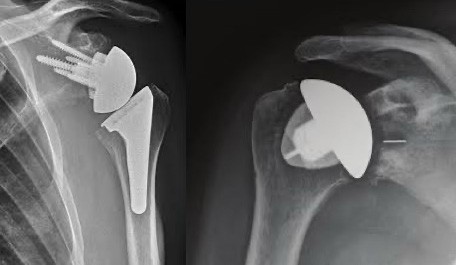

Wenn konservative Therapien nicht mehr helfen, kann eine Schulterprothese die Lebensqualität enorm verbessern. Aber wie sorgt man dafür, dass das neue Gelenk wirklich perfekt passt? Die Antwort: mit moderner 3D-Planung!

Eine 3D-geplante Schulterprothese ist ein künstliches Schultergelenk, das mithilfe modernster Bildgebung exakt an den Körper des Patienten angepasst wird. Vor der Operation wird ein spezielles CT (Computertomografie) durchgeführt. Aus diesen Bildern wird ein dreidimensionales Modell der Schulter erstellt.

Dieses Modell zeigt genau, wie Knochen und Gelenk aufgebaut sind – auch kleine Abweichungen oder Schäden werden sichtbar. So kann Dr. Lucie Strehn die Operation optimal vorbereiten und die Prothese ganz individuell anpassen.